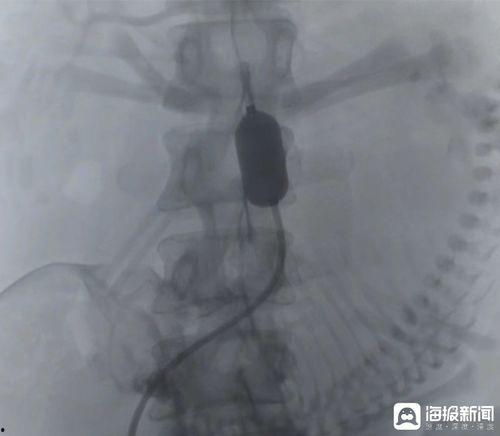

你有没有想过,医生在进行成人股动脉穿刺时,是如何精准定位穿刺点的呢?今天,就让我带你一探究竟,揭开这个神秘过程的神秘面纱!一、股动脉穿刺点定位的重要性首先,得说说股动脉穿刺点定位的重要性。这可不是闹着玩的,它关系到手...